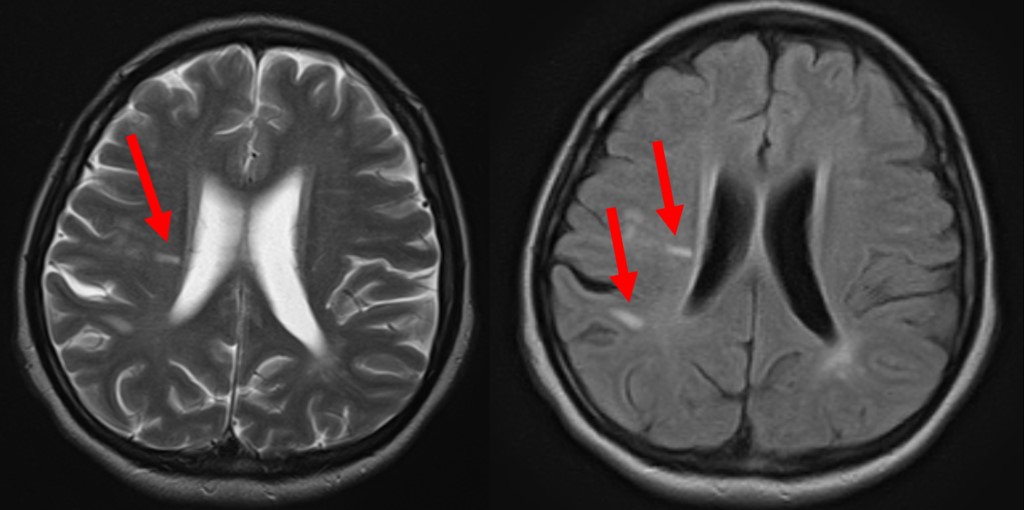

MSの痙縮は、動きを制御する神経を覆うミエリンの損傷により発生します。この損傷により、神経インパルスが遅くなったり、停止したりして、神経学的問題が生じます。

MS は、免疫系がミエリン鞘またはミエリン鞘の生成と維持に関与する細胞を誤って攻撃する自己免疫疾患です。この攻撃は炎症を引き起こし、ミエリン鞘と、最終的にはミエリン鞘を取り囲む神経の両方に損傷を与えます。

硬化症という言葉は、MS における神経とそのミエリン鞘の複数の領域の瘢痕化を指します。